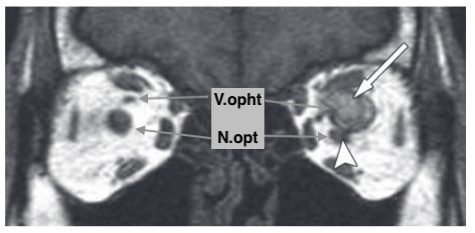

Thrombose de la veine ophtalmique supérieure

- Dans les sinusites ++

- Douleurs orbitaires, proptose, symptomes visuels…

- Elargissement de la veine

- Hyper T1

- Déplacement inférieur du nerf optique